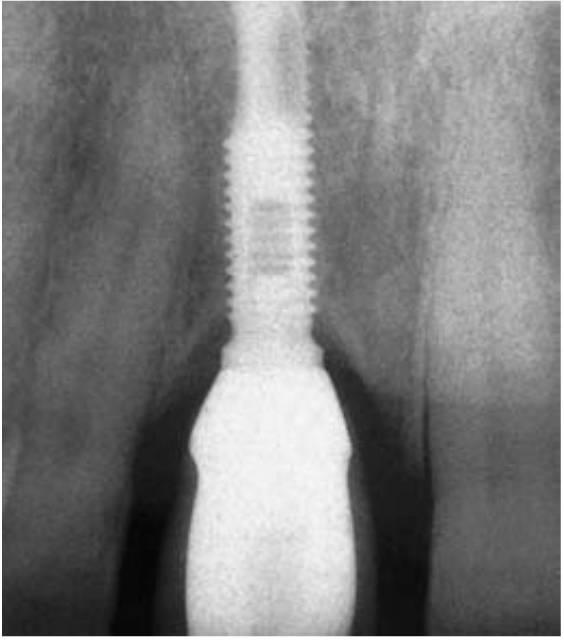

Muchos protocolos quirúrgicos recomiendan la colocación de implantes endósticos por debajo o en la misma cresta del reborde durante la primera fase quirúrgica. La conexión pilar-cuerpo del implante puede compararse con el margen de una corona. Berglundh y cols observaron en perros una pérdida ósea de 0,5 mm por debajo de la conexión pilar-cuerpo del implante durante las dos semanas siguientes a la fase II de reentrada y conexión de pilares (fig. 4-14). Lindhe y cols observaron un tejido conjuntivo inflamado extendiéndose 0,5 mm por arriba y por debajo de esta conexión de pilar a implante. Wallace y Tamow afirmaron que la anchura biológica se forma también con los implantes y puede contribuir a parte de la pérdida ósea marginal observada. La teoría de la anchura biológica parece atractiva para explicar la falta de pérdida ósea entre la primera fase quirúrgica y la pérdida ósea inicial observada durante el primer año después de la segunda fase de colocación del pilar. En cualquier caso, debería considerarse que la anchura biológica en los implantes, tal y como se ha observado, suele incluir la profundidad del sulcus, mientras que la anchura biológica del diente natural no la incluye.

La grieta entre el tornillo de cierre y el cuerpo del implante durante la cicatrización inicial es similar a la grieta de la conexión pilar-implante. No obstante, el hueso puede crecer por encima del tornillo de cierre, y por tanto la grieta en sí misma, no tiene porque ser la causa de la pérdida ósea. La grieta entre el implante y la conexión del pilar ha sido denominada «microgap» (microespacio). La dimensión actual de esta conexión suele ser de 0 μm y tiene una conexión directa metal-metal. En cualquier caso, cuando este espacio es expuesto al entorno oral, se suele observar una pérdida ósea de por lo menos 0,5 mm por debajo de la conexión.

Es cierto que, la pérdida ósea se produce alrededor de una conexión pilar-implante expuesta colocada debajo del hueso y que se observa de las 2 a las 4 semanas siguientes, una vez que la conexión queda expuesta al entorno oral. La pérdida ósea se produce en ocasiones antes de la carga del implante con la prótesis. Es lógico llamar a esta pérdida ósea marginal la anchura biológica.

La pregunta primaria persiste, cuando el cirujano coloca la conexión pilar-implante en zona infraósea, ¿cuánta pérdida ósea se debe a la anchura biológica del implante, y por tanto fuera de la influencia del odontólogo? Diferentes estudios en la literatura observan que la micro y macrogeometría pueden afectar a las dimensiones de la anchura biológica o a la cantidad de pérdida ósea temprana.

La pérdida ósea observada hasta la primera rosca implica que la cantidad de hueso perdido es similar para diferentes diseños de implantes. En cualquier caso la primera rosca se encuentra a una distancia diferente del margen del pilar según el diseño del implante. Se ha asociado una mayor pérdida ósea a un collar pulido de 4 mm infraóseo que a uno de 2 mm. El concepto de anchura biológica del implante no explica completamente la cantidad total de pérdida ósea vertical observada. Además la cantidad de pérdida ósea producida por la anchura biológica se produce durante el primer mes, esté cargado o no el implante, y está relacionada con el diseño del módulo crestal del implante y la posición de la conexión pilar-implante en relación con el hueso pero no está relacionada con la densidad del hueso. Este concepto no explica por qué se observa con más frecuencia una mayor pérdida ósea después de la carga en el hueso blando en comparación con un hueso más denso, como tampoco explica la mayor media de fracasos de implante en hueso de menor calidad después de la carga.